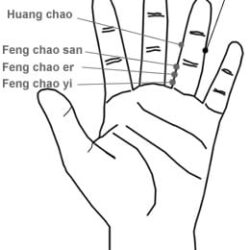

11.17 עץ Mù 木

מיקום שתי נקודות, בחלק המדיאלי של האצבע המורה, על הצד הפלמרי של קו ה- D, הנקודות צמודות למפרק המטא פלנגיאלי. Dr Li Guo Zheng: יש שלוש נקודות באזור הזה. שם הנקודה Mù 木 – עץ. דיקור 0.3 – 0.2 צון קרוב לעצם. במחלות עור של הידיים דוקרים את הנקודה בצד של המחלה, למחלות האחרות דוקרים […]